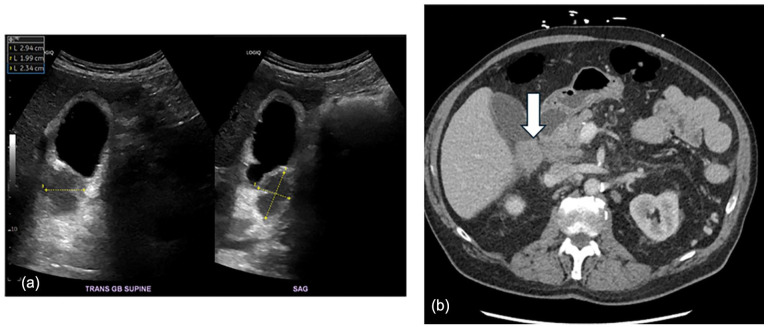

Primary follicular lymphoma (PFL) is an indolent subtype of non-Hodgkin lymphoma that typically involves lymphoid tissues. Gallbladder involvement is exceedingly rare and poses significant diagnostic challenges. Few cases in the literature describe gallbladder follicular lymphoma, particularly in elderly male patients, leaving notable gaps in clinical understanding and management. Herein, we present the case of an 82-year-old male who presented with acute abdominal pain and unintentional weight loss. Initial imaging, including contrast-enhanced computed tomography, ultrasound, and magnetic resonance imaging, revealed a suspicious gallbladder mass with wall thickening and regional lymphadenopathy, raising concern for malignancy. Endoscopic ultrasound-guided fine needle aspiration and subsequent immunophenotyping confirmed a diagnosis of PFL. The patient underwent radical cholecystectomy with lymphadenectomy, and histopathological examination corroborated the diagnosis of gallbladder follicular lymphoma. During follow-up, the patient developed complications, yet no evidence of lymphoma recurrence was observed. A literature review identified 8 similar cases, further emphasizing the rarity of this presentation. Future research should focus on optimizing diagnostic techniques, refining therapeutic strategies, and conducting longer-term follow-up studies to better assess patient outcomes in such a rare disease. This case highlights the need for heightened clinical suspicion and comprehensive evaluation in atypical presentations of extranodal lymphoma.